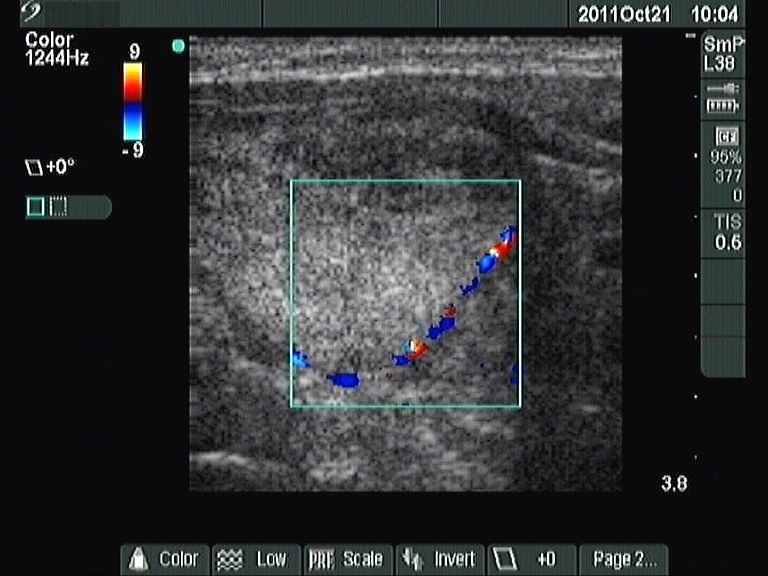

Follow-up examination 2 years later (2nd and 3rd rows of images):

Ultrasonography: was unchanged except for the increase of the left lobe by 38% in volume.Cytology: benign lesion.

The patient was operated on because of compression signs.

Histopathology: Hashimoto's thyroiditis and multiple hyperplastic nodules in the left lobe.

It is worth comparing the numerous small echonormal lesions and the large nodule in the left thyroid. The former are part of the so-called pseudonodular form of Hashimoto's thyroiditis, while the true nodule was much larger. Pseudonodules are usually in the range of 5 to 15 mm in maximal diameter.

Most solitary nodules which are greater than 2 cm in maximal diameter, display a halo sign and perinodular blood flow are proved to be follicular tumor. This case belongs to the relatively rare exceptions.